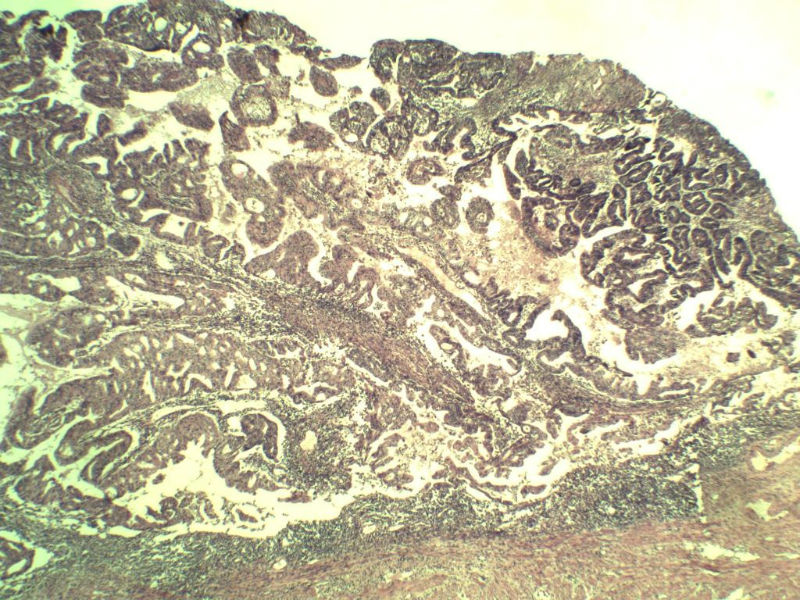

女,57岁,全切子宫一个,宫体体积 9 × 8 × 7 cm3,肌壁厚 2.5 cm,内膜菲薄,部分区域增厚达 0.4 cm(约3*2.5cm区域)。 请问各位老师  这个可以诊断子宫内膜癌了吧?      深肌层没有看到浸润。

患者因"发现下腹部包块1月多"入院  宫体体积 9 × 8 × 7 cm3,肌壁厚 2.5 cm,内膜菲薄,部分区域厚 0.4 cm(约3*2.5cm)。宫颈结构不清,长约 2.5 cm,表面欠光滑。临床诊断宫颈宫腔积液.

宫内膜样腺癌

筛状、迷路样结构

间质消失或者纤维性间质

子宫内膜样腺癌

高分化子宫内膜样癌。浸润浅肌层(深度<1/3肌层)。根据FIGO2009分期,子宫内膜癌局限于内膜层和<1/2肌层,都属于IA期。二者处理不再区别对待。